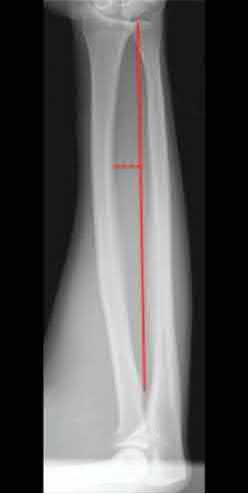

A 25-year-old female is involved in a motor vehicle collision. She presents with the isolated injury seen in Figures A through D. Her leg is swollen but her skin is intact. She has no clinical signs of compartment syndrome. Which of the following treatment options will allow for maintenance of fracture alignment and minimize the risk of soft tissue complications?

The patient presents with a closed distal third metaphyseal-diaphyseal distal tibia fracture with simple intra-articular extension. Immediate intramedullary nailing along with percutaneous fixation of the articular component provides appropriate restoration of length, rotation and alignment and minimizes the risk of wound complication.

Displaced distal third tibia fractures may be associated with simple intraarticular extension. Operative treatment of intra-articular distal tibia fractures has historically been performed with open reduction and internal fixation. Early open reduction and plate fixation of pilon fractures has been associated with high rates of infection and wound complication. In select patterns with simple articular extension, percutaneous screw fixation and medullary nailing may provide appropriate reduction with minimal soft-tissue risk.

Marcus et al. evaluated the outcomes of immediate intramedullary nailing and percutaneous fixation of simple intra-articular distal tibia fractures (AO/OTA 43 C1 and C2). The authors found excellent rates of union and alignment, however caution against broad application of this technique until more rigorous randomized studies can be performed.

Sirkin et al. retrospectively evaluated the results of a staged approach to management of intra-articular distal tibia fractures with temporary bridging external fixation followed by open reduction and internal fixation (ORIF). The authors found decreased rates of wound complication and infection compared with prior studies.

Figures A and B demonstrate a distal third tibial shaft fracture with simple intra-articular extension. The axial and coronal CT cuts in Figures C and D further clarify the articular injury. Illustrations A and B demonstrate a comminuted distal third tibial fracture with simple intra-articular extension. Illustrations C and D are fluoroscopic images of the same injury after intramedullary nailing and percutaneous fixation of the articular component.